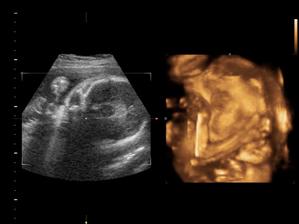

Nas anjelik Alex

Zatial este schovany v brusku ale uz coskoro sa z neho potesime aj nazivo 🙂) Lubime nasho Alexa uz od sameho zaciatku 🙂